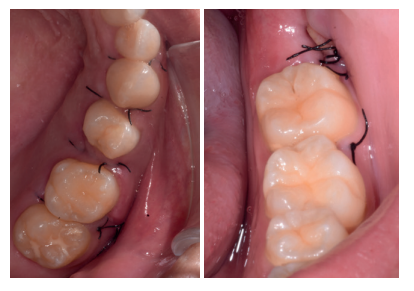

Caso clínico: se presenta un caso clínico de una mujer de 20 años, sin antecedentes médico-quirúrgicos de interés, que acudió a consulta remitida por su ortodoncista, para la extracción de un premolar maxilar retenido, en posición invertida. Tras la extracción del premolar y del tercer molar inferior retenidos, se obtuvo dentina procedente de ambos, para la regeneración ósea guiada del defecto resultante de la extracción del premolar, realizando revisiones a la semana y a los 4 meses de la intervención.

Clinical case: a clinical case of a 20-year-old woman is presented, with no interesting medical record, who went to dental clinic for removal of an inverse maxillary bicuspid retained. After maxillary bicuspid and lower third molar extractions, autogenous dentin was obtained from both teeth, to perform a guided bone regeneration of the bicuspid defect. A week and 4-month check-up were carried out.